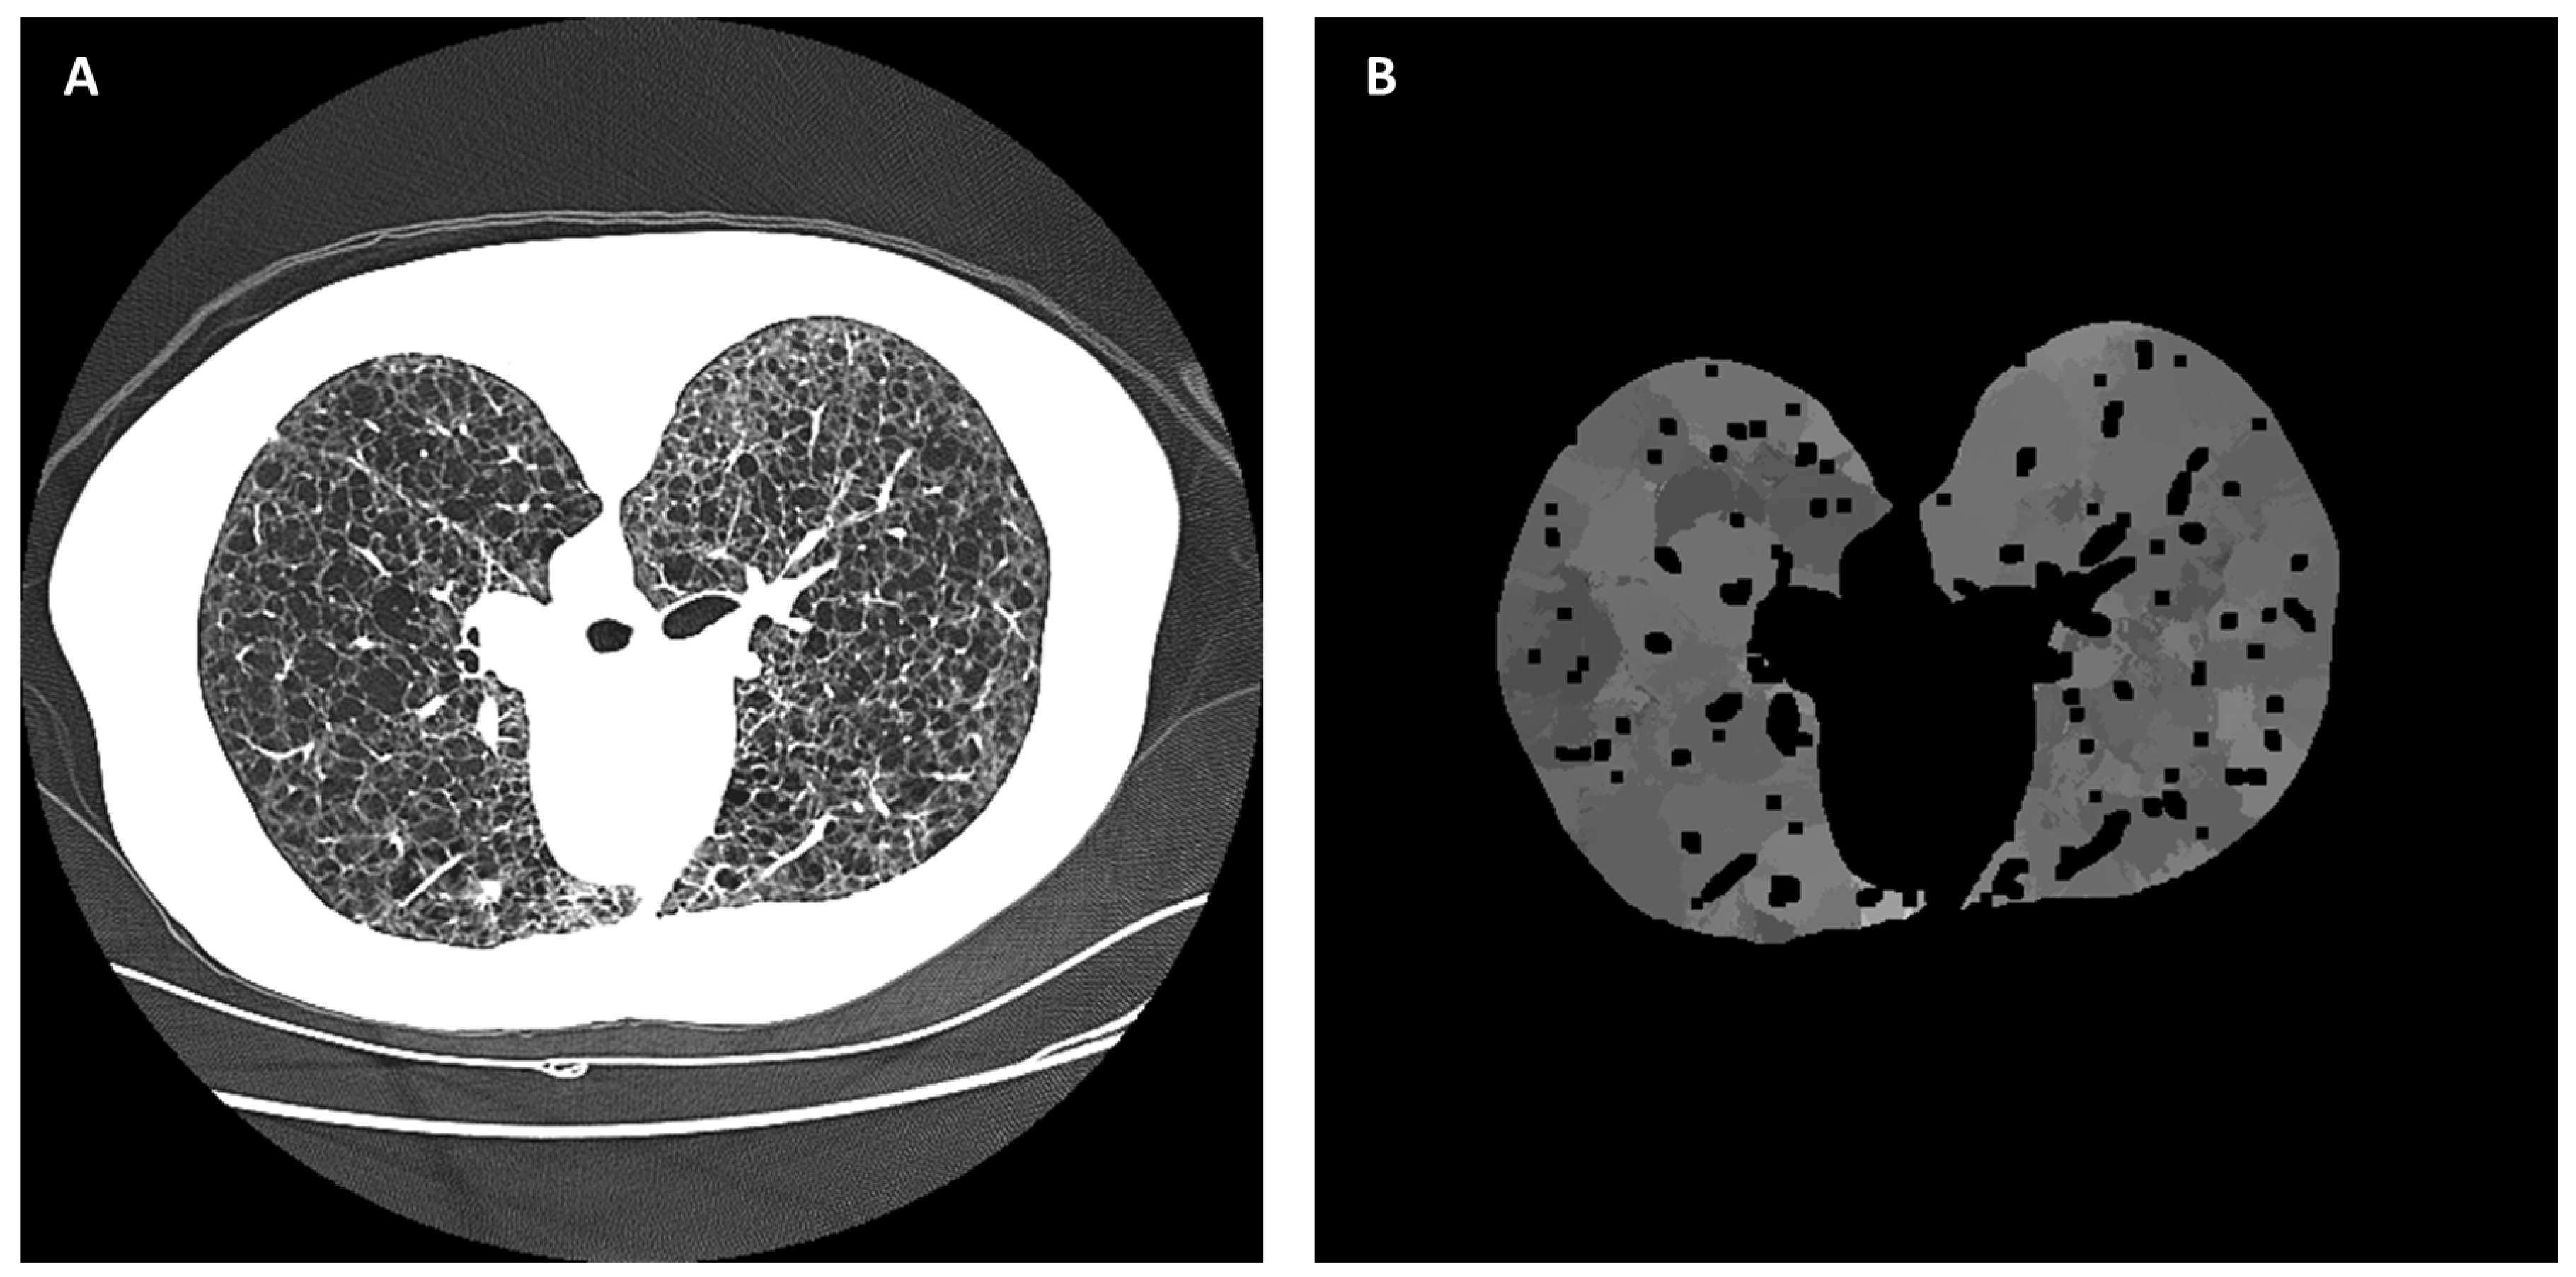

Figure 8.

An example of deriving the radiodensity distribution of non-cystic parenchyma in the lungs by a local smoothed histogram filter. (A) The raw HRCT section is displayed on a grayscale of −1100 HU to −500 HU. (B) The calculated radiodensity distribution of non-cystic parenchyma in the lungs. The dark voids in the distribution are areas of bright vessels.

The next module determined the typical radiodensity of non-cystic parenchyma for all locations in the lungs. In each CT section, a locally smoothed histogram filter was applied to the radiodensity values of all areas in the lungs, excluding the previously segmented large airways and large vessels. The histogram window was a circular area of 35 mm in diameter with a smoothed Gaussian profile that gave more weight to pixels near the center of the window. At each image pixel, a weighted frequency histogram within the radiodensity range of Iair(z)+25 and −500 HU was calculated from the values of all pixels within the histogram window centered at the pixel. This range of radiodensity excluded large air voids and blood vessels. Then, the radiodensity of the local non-cystic parenchyma, Ip(x, y, z), was defined as the dominant mode of the local histogram. An example of the raw CT image (Figure 8A) and the calculated image of the radiodensity of non-cystic parenchyma (Figure 8B) are given in Figure 8. It should be noted that the histogram filter would not yield results at the centers of cysts or air voids if they were larger than the histogram window. However, as explained below, this would not affect the identification and segmentation of the cysts.